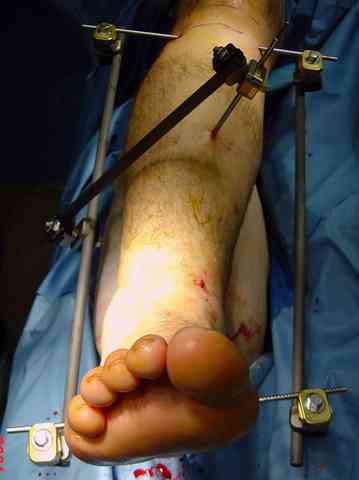

В первые часы после поступления больным экстренно накладывается простой фиксатор из двух поперечно проведенных стержней или сооружается "Delta

Frame" в зависимости от места локализации, и проводится дистракция.

Преимуществ у временного фиксатора много, во первых больной независим, если по другим показаниям нет необходимости находиться в стационаре, то больной может быть выписан домой с возможностью в амбулаторных условиях оценивать состояния мягких ткани на готовность к операции.

Наружным фиксатором обеспечивается длина конечности, предупреждается вторичное сокращение мягких ткани, что является немаловажным фактором для заживления послеоперационных ран. Без фиксатора сокращенные мягкие ткани легко травмируется во время манипуляций, трудно будет провести репозицию, ухудшается местное кровообращение и сохраняется посттравматический отек.

Здесь выставлена пара случаев перелома пилона, оба

случая леченные этапным наружным фиксатором.

Второй случай фиксирован аппаратом Илизарова.